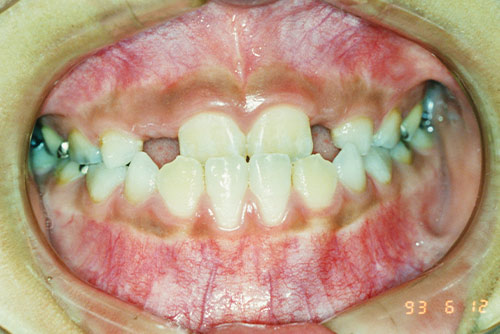

小さな顎に大きな歯が生えると、どうしても歯並びが悪くなります。通常の矯正治療は、ガタガタになった歯を整えるものですが、根本的な治療にはなりません。時間が経つと、歯並びが後戻りすることからも分かります。

歯並びも同じで、「顎のスペースが狭い」と歯が重なりながら生えるしかなく(「叢生」)、結果としてデコボコの歯並びになります。